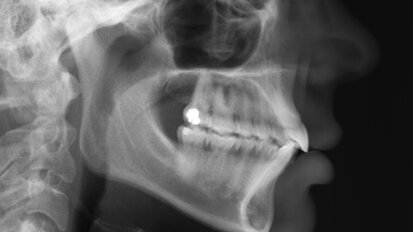

Rehabilitace Straumann